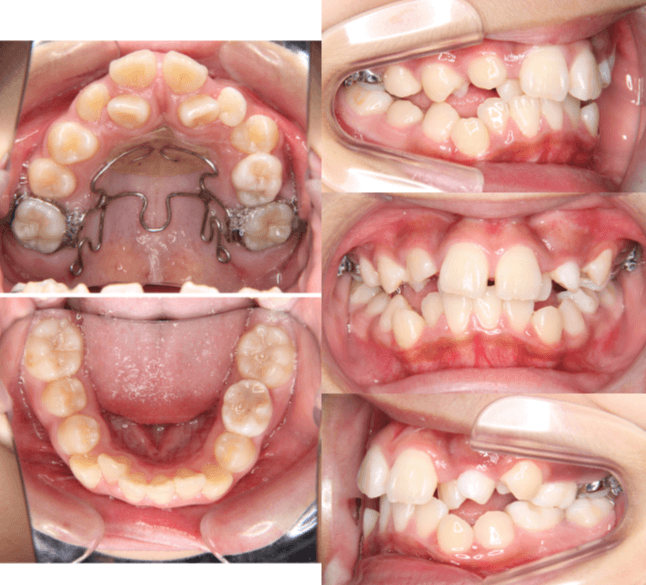

| 年齢・性別 | 11歳1ヶ月の女性 |

|---|---|

| 主訴 | 口元の突出感と歯並びが気になり、将来的な咬合状態を整える目的で来院された患者様です。 |

| 治療期間・回数 | 2年6ヶ月・25回 |

| 費用 | 720,000円 |